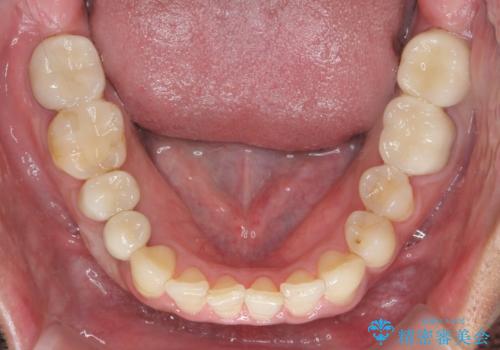

- 30代男性

- 1年8ヶ月

- 長年虫歯の治療を受け続けたことで銀歯・コンポジットレジン修復だらけになってしまい、今後の見た目や歯を大切にするためにセラミック治療矯正治療を希望され来院されました。

マイクロスコープを用いた精密根管治療やセラミック治療、マウスピース矯正治療を一つの医院で行うことのできる当法人ならではの総合歯科治療を実践していきます。

歯並びを整えたことで、歯ブラシのしやすさが向上し見た目も銀歯を全て除去したことで大きく改善して大変満足いただくことができました。